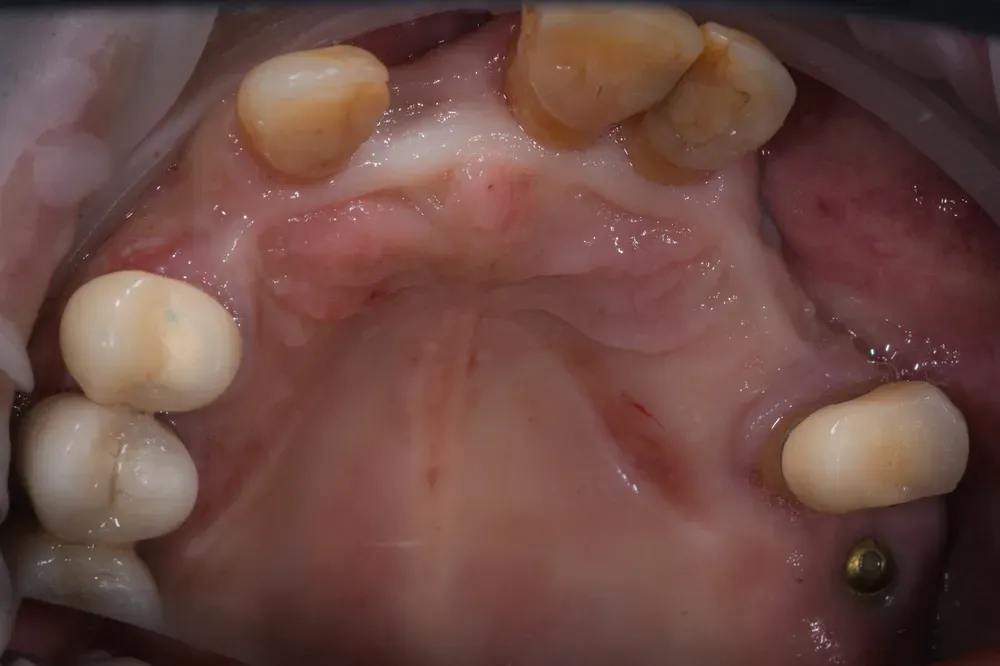

Nelle due figure sottostanti è evidente come la terapia, qui ancora in fase di estrazione dei denti non mantenibili, ottenga il ripristino totale (la rigenerazione) del tessuto alveolare e quindi una forma del tutto simile a quella naturale. E questo si ottiene solo con l’espansione mucosa del sito e senza xenoinnesti di connettivo. Inoltre, nei siti (alveoli) estrattivi non è stato inserito nulla per mantenere la forma: il mantenimento si ottiene solo con la forma del provvisorio che si inserisce per 4 mm all’interno con i “ponti ovoidi”.

Abbiamo fatto una scansione con scanner intraorale per finalizzare il lavoro con la ceramica e, grazie ai nuovi denti che sono stati resi possibili dalla forma delle gengive che vedete nelle immagini sottostanti, egli ha ripreso la sua vita dinamica, più felice di prima, con la possibilità di godere appieno di ogni sua giornata grazie anche ai suoi nuovi denti! E lui si merita tutto ciò e anche di più: credetemi.

Quanto tempo impiega la rigenerazione totale dell’arcata? Con il protocollo descritto (ponte provvisorio con ponti ovoidi), la rigenerazione della forma anatomica della mucosa e dell’osso avviene in circa 4-6 mesi. Il carico protesico definitivo in ceramica può seguire dopo la stabilizzazione tissutale.